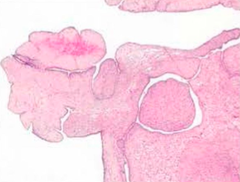

Ductal Carcinoma In Situ (DCIS or Intraductal Carcinoma)

Malignant proliferation of cells in ducts that does not invade into BM (no mass) Pathogenesis: center of mass dies (necrotic) and becomes calcified (detectable on mammography) Camedo-type: necrosis and calcification in center Paget: DCIS that extends up to the nipple up to the skin --> eczematous changes (underlying carcinoma)